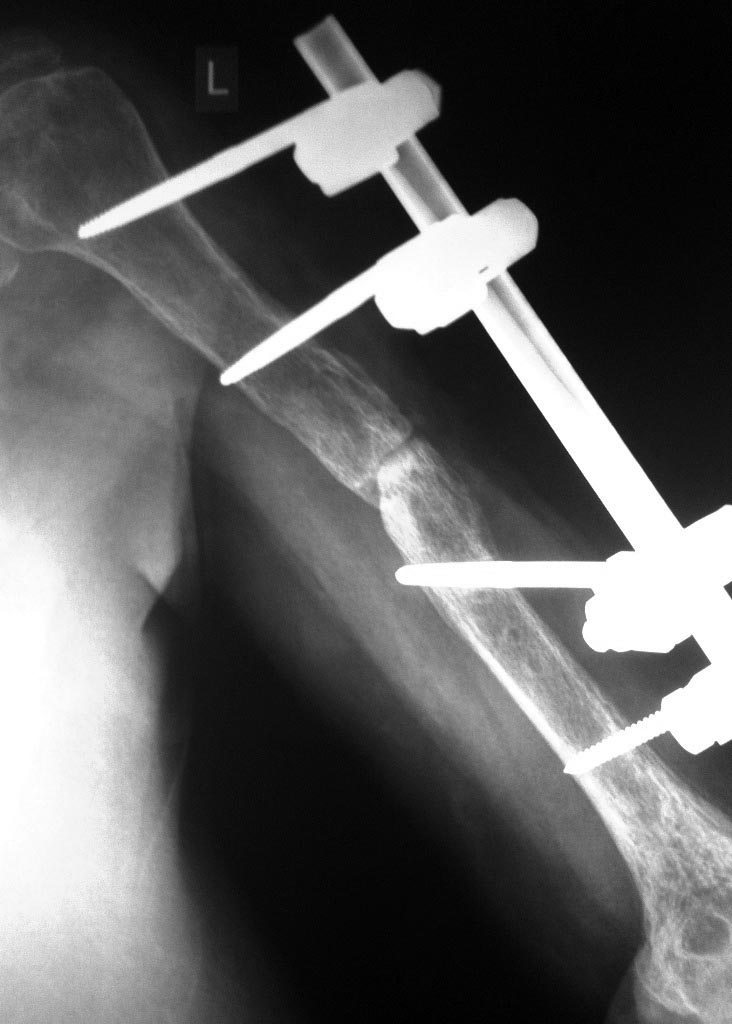

Обратилась пациентка с ложным суставом средней трети левого плеча стабилизированный в стержневом АВФ.

анамнез - 01.01.16г. получила закрытый перлом средней трети левой плечевой кости.

05.01.16г. оперирована - МОС пластиной;

20.01.16г. вскрытие нагноившейся гематомы плеча;

16.02.16г. - удаление металлоконструкции, стабилизация АВФ левой плечевой кости (по выпискам по поводу хронического остеомиелита);

20.04.16г. - костная пластинка зоны перелома, перемонтаж АВФ.

Сейчас - кожный покровы без признаков восполнения, температура в пределах нормы на протяжении всего периода после закрытия раны (с февраля), свищей не было. Локтевой без контрактуры, в плечевом есть ограничение объёма движения.На Rg - признаки атрофического ложного сустава, локунарный остеопороз (секвестров либо периотсальной реакции вроде бы как нет). Рассматриваем вариант БИОС+костная пластика (если не удастся закрыто), но вот данные в медицинской книжке об перенесённом остеомиелите настораживают.

Атрофическое инфицированное несращение. Если есть возможность нужно сделать КТ (для определения поражения кости и наличия секвестрации).

Спасибо за ответ. К сожалению снимков после первых двух операций нет. Последний рентген после перемонтажа АВФ и костной пластики низкого качества.